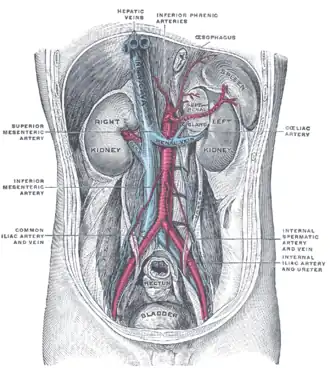

Posterior abdominal wall, after removal of the peritoneum, showing kidneys, suprarenal capsules, and great vessels.

Posterior abdominal wall, after removal of the peritoneum, showing kidneys, suprarenal capsules, and great vessels. -